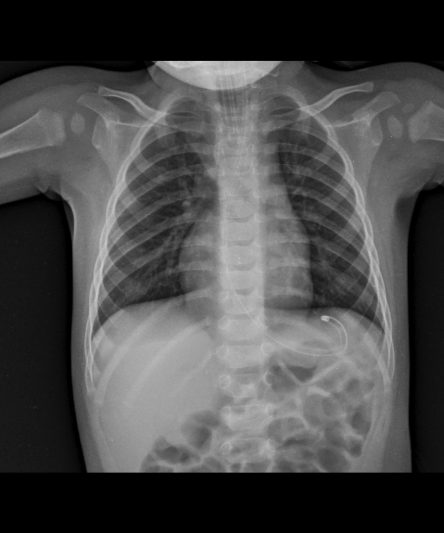

Microskan with Ultra high frequency can take the Lateral Lumbar Spine image of a 90 kg Patient with the correct image receptor